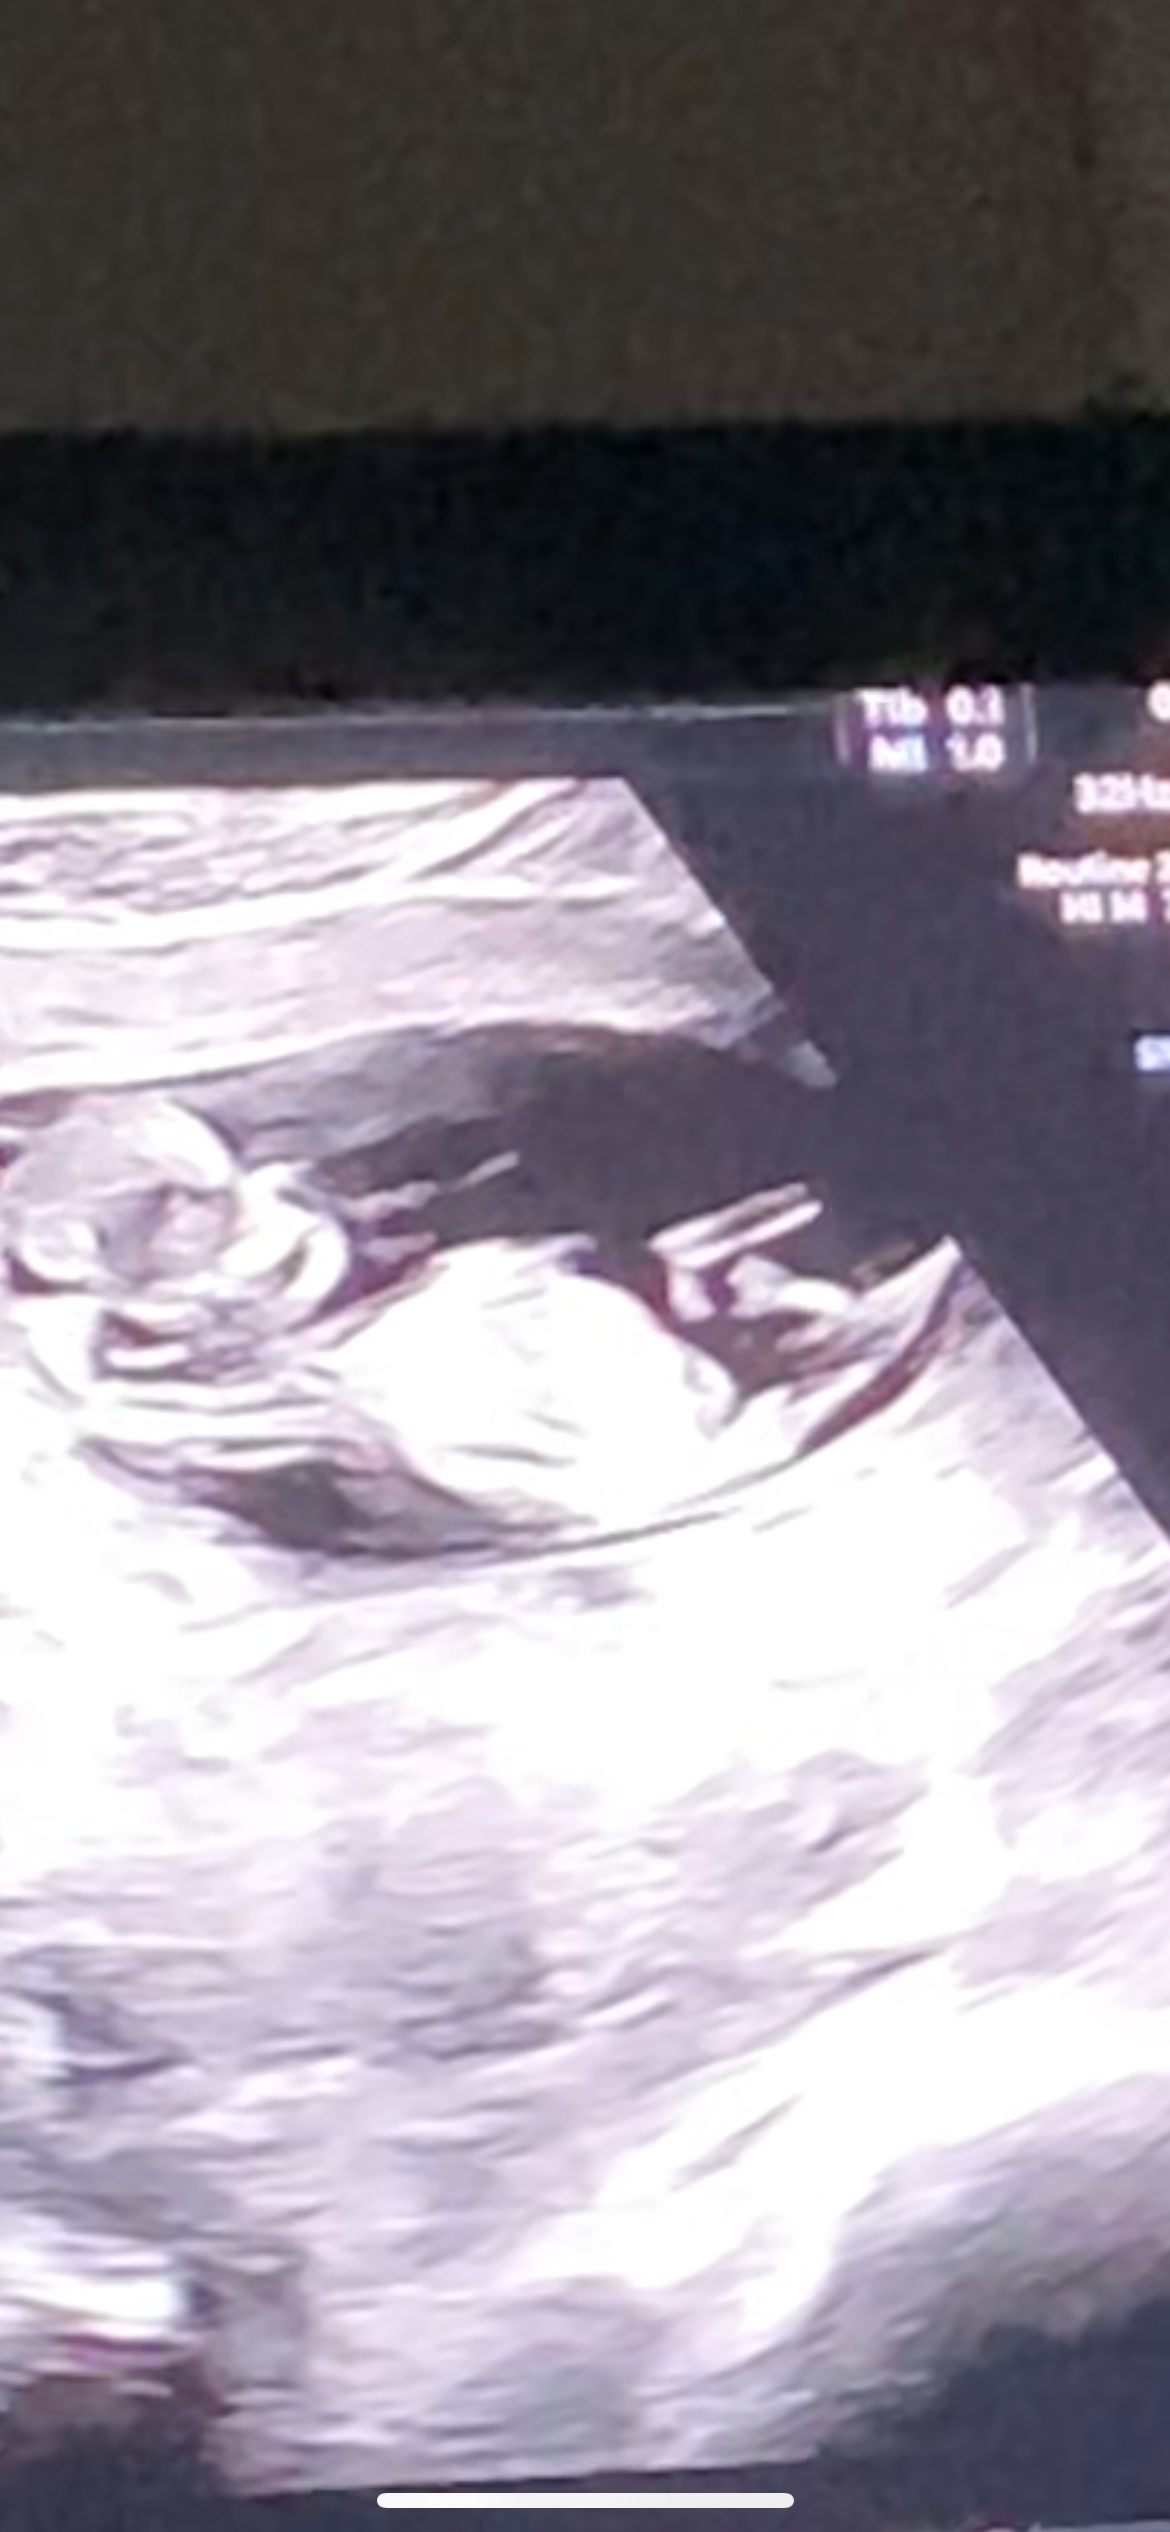

Мальчик или девочка?

Анализы, скринингиПриветик! Кто разбирается, мальчик или девочка, что видите?))

Девочка

Малина Малиновая, кости таза, лонное сочленение возможно, но половые губы так не выглядят, особенно сбоку) На узи чем белее и контрастнее ткани, тем они плотнее, так выделяться могут только хрящи или косточки